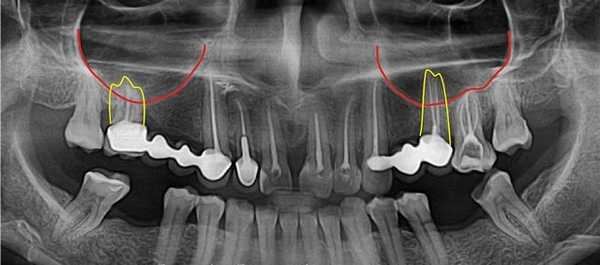

Ороантральное соустье - это ятрогенное состояние, которое может являться как осложнением хирургических стоматологических операций, так и эндодонтического лечения. Перфорация верхнечелюстной пазухи чаще всего возникает при проведении следующих процедур:

- Удаление зуба. Большая часть осложнений развивается после экстракции первых моляров верхней челюсти, реже - вторых и третьих моляров (зубов мудрости), премоляров, корни которых располагаются непосредственно в гайморовой пазухе. Ороантральная перфорация также может стать следствием неосторожного кюретажа лунки удаленного зуба.

- анатомические особенности зубов и челюстей: расположение корней премоляров и моляров в полости пазухи, длинные расходящиеся корни, атрофия костной ткани;

При пневматическом типе строения слизистая оболочка гайморовой пазухи отделена от корней зубов тонкой кортикальной пластинкой или непосредственно соприкасается с ними. Поэтому любая травматичная стоматологическая манипуляция (эндодонтическая, хирургическая) способна привести к прободению дна пазухи. Перфорацией принято считать дефект давностью не более 3-х недель. В дальнейшем происходит эпителизация хода с формированием свища.

КТ придаточных пазух носа. Тотальное снижение пневматизации правой в/челюстной пазухи на фоне нарушения целостности и элевации ее дна (красная стрелка) вблизи корней 1-го моляра (синяя стрелка).